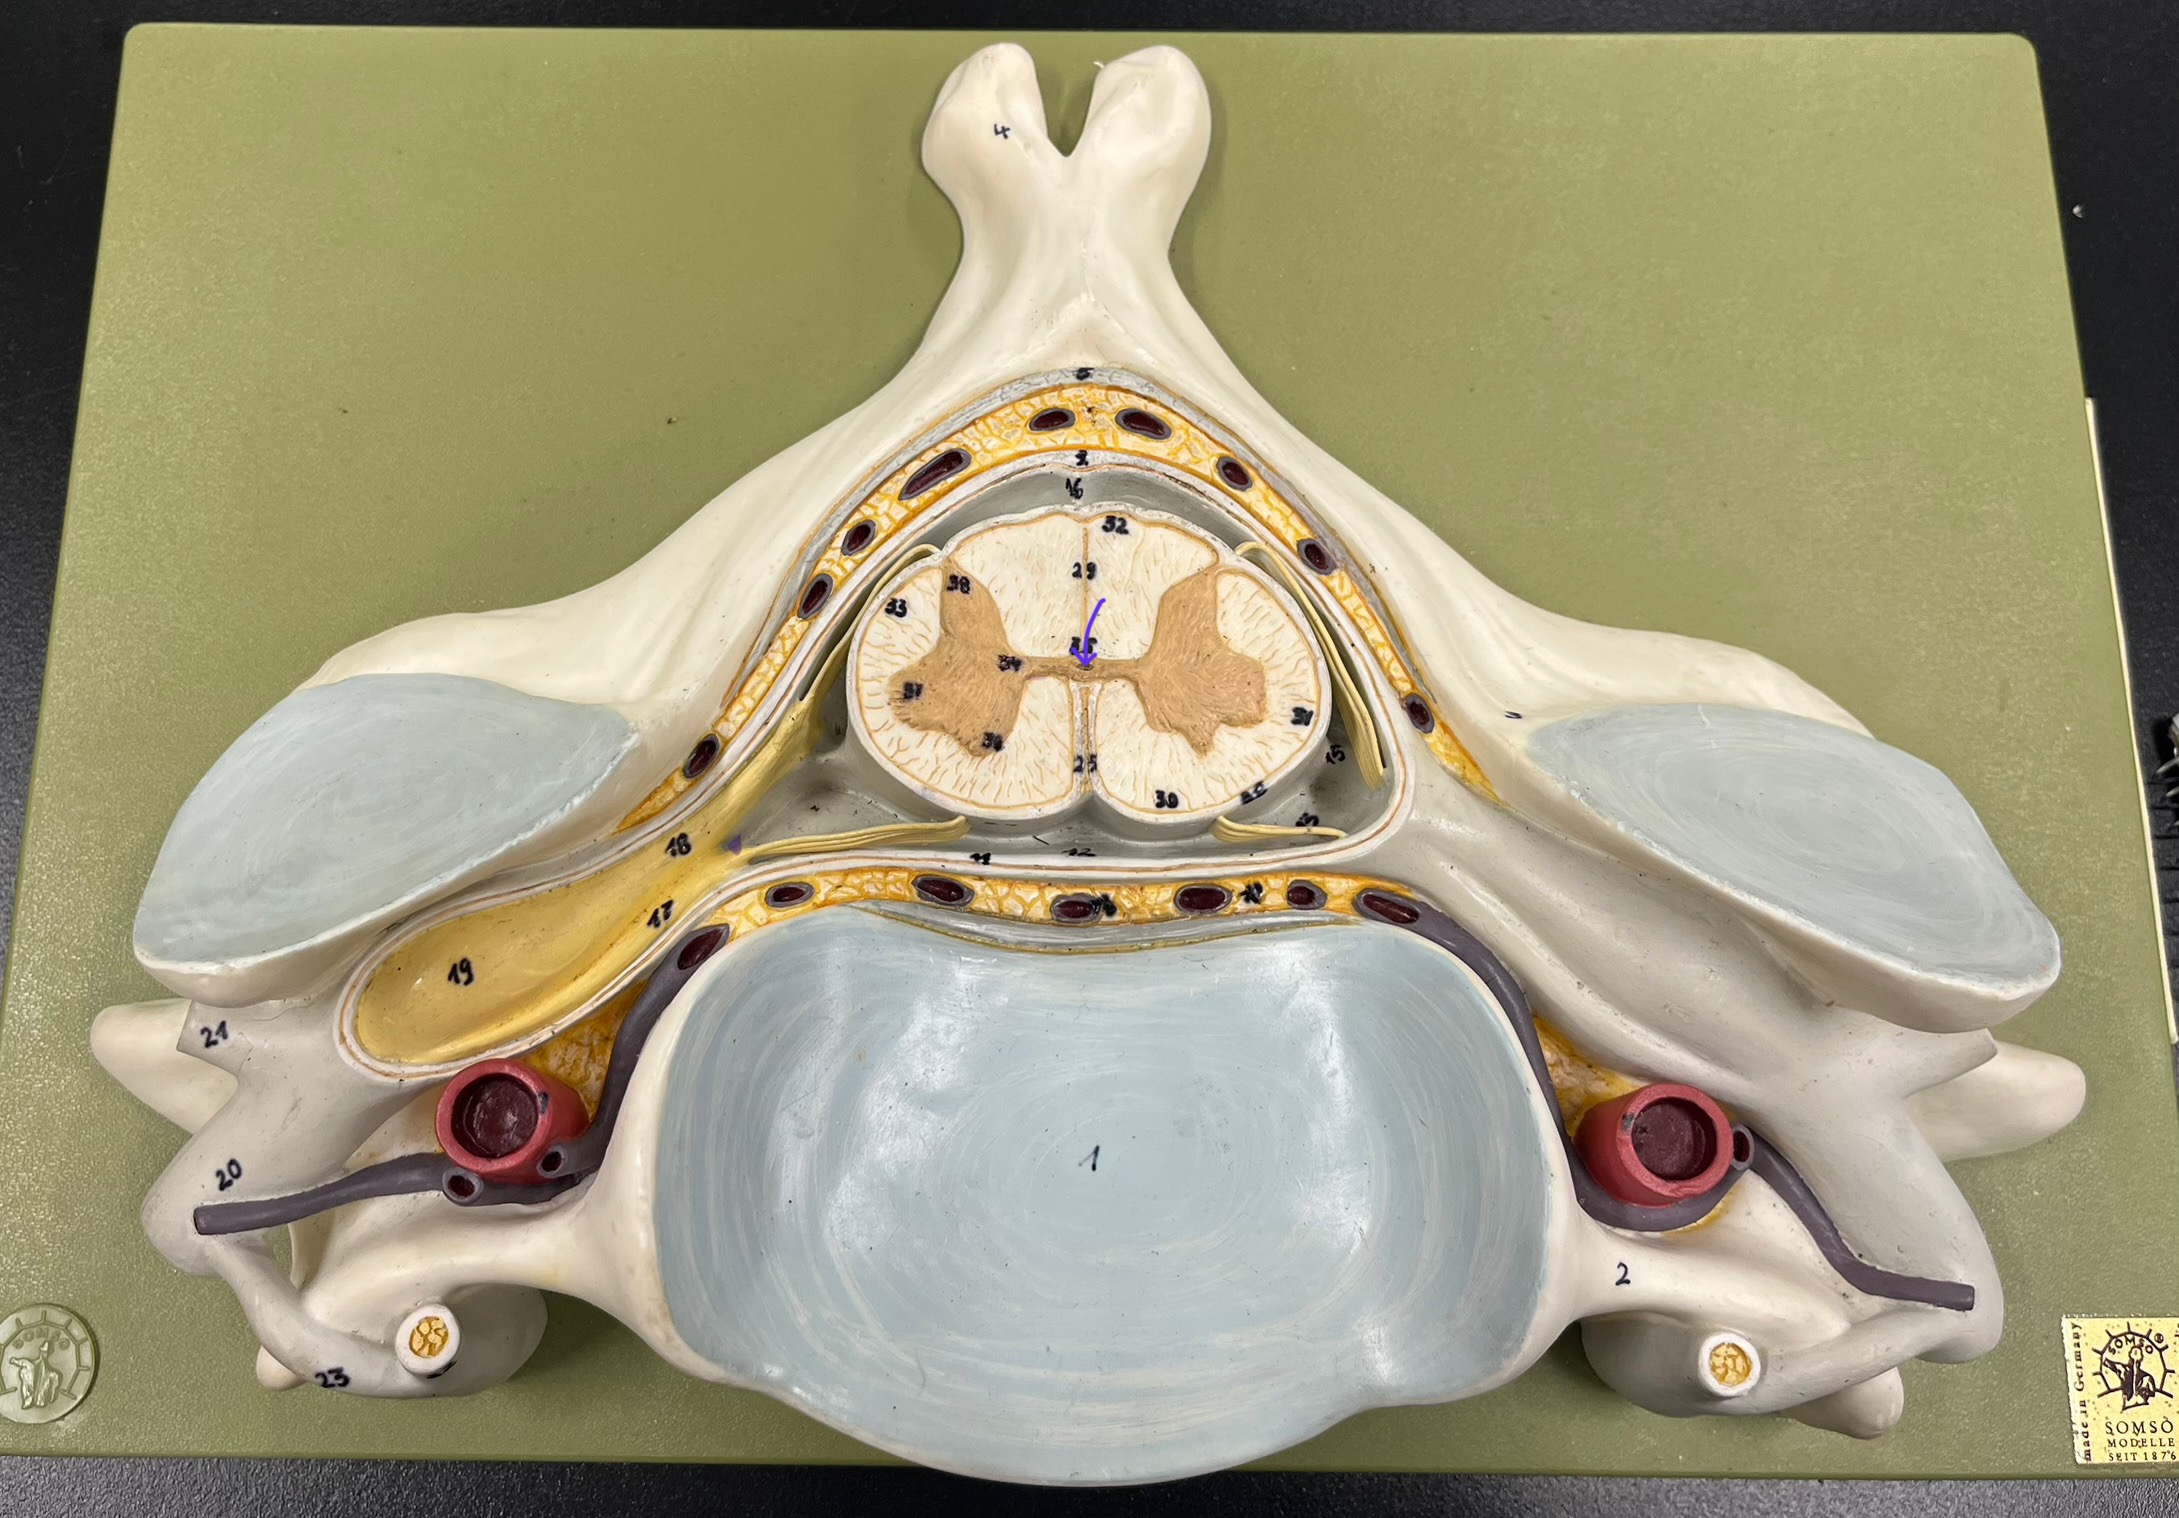

epidural space

dura mater

subdural space

arachnoid mater

subarachnoid space

pia mater

denticulate ligaments

What is the groove here?

anterior median fissure

posterior median sulcus

posterior (dorsal) horn

posterior (dorsal) horn; R—>L

anterior (ventral) horn

lateral horn (selected models)

gray commissure

central canal

anterior column

lateral column

posterior column

white commissure

posterior (dorsal) root ganglion

What is the bulb here?

posterior (dorsal) root ganglion

posterior (dorsal) root

posterior (dorsal) root

anterior (ventral) root

anterior (ventral) root

dorsal ramus

dorsal ramus

ventral ramus

ventral ramus

rami communicantes

rami communicantes

sympathetic chain ganglia

sympathetic chain ganglia